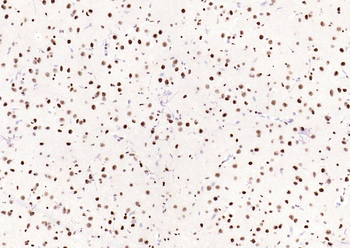

Phospho-Smad3 (Ser423 + Ser425) Rabbit Polyclonal Antibody [orb6983]

FC, IF, IHC-Fr, IHC-P, WB

Bovine, Canine, Equine, Gallus

Human, Mouse, Porcine, Rat

Rabbit

Polyclonal

Unconjugated

100 μl, 200 μl, 50 μlPhospho-SMAD5 (Ser463 + Ser465) Recombinant Rabbit Monoclonal Antibody [orb559123]